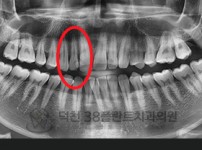

치료전후